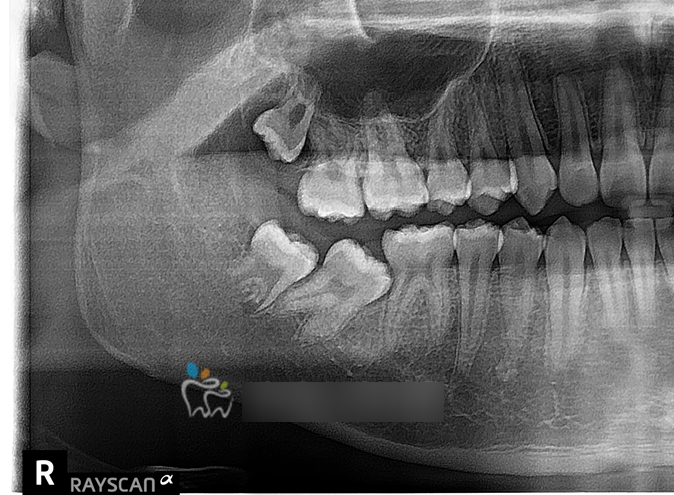

돌출입 교정, 잇몸돌출, 아래앞니 덧니 교정

돌출교정, 발치교정 옥니안되게 교정치료 - 청소년 교정치료

쓰러진 어금니 세우기, 청소년교정, 어금니 부분교정 - 잠실

쓰러진 어금니 세우기, 청소년교정, 어금니 부분교정 - 잠실 안녕하세요 교정전문의 최혜영 원장입니다. 잘...